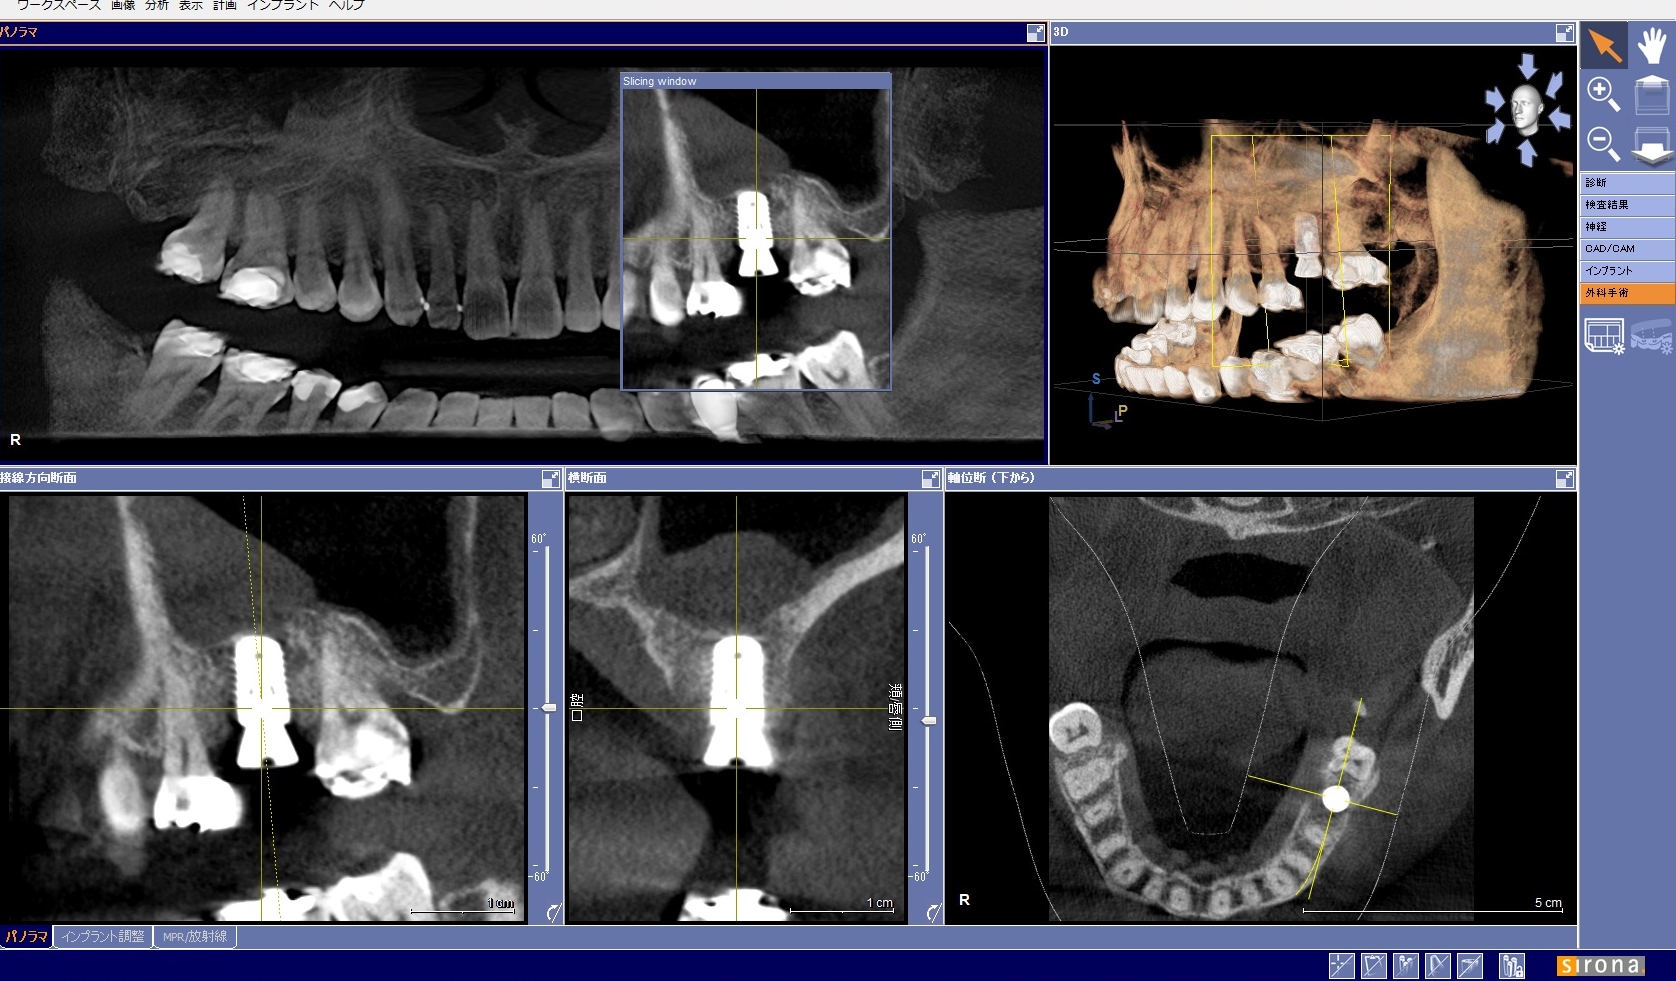

セレックでバーチャルワックスアップを行い、その3次元画像をギャラクシスというプランニングソフトにインポートしてCTの3次元画像と重ね合わせます。

それを用いて、インプラントのポジションをプランニングします。今度は、そのデータを再びセレックへインポートしてサージカルガイドを削り出します。

オペ後のCTですが、上顎洞底までの骨を有効に使って正確な位置に埋入できます。